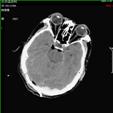

2).颅后窝血肿术前 术后

3).颅骨凹陷性骨折术前 术后